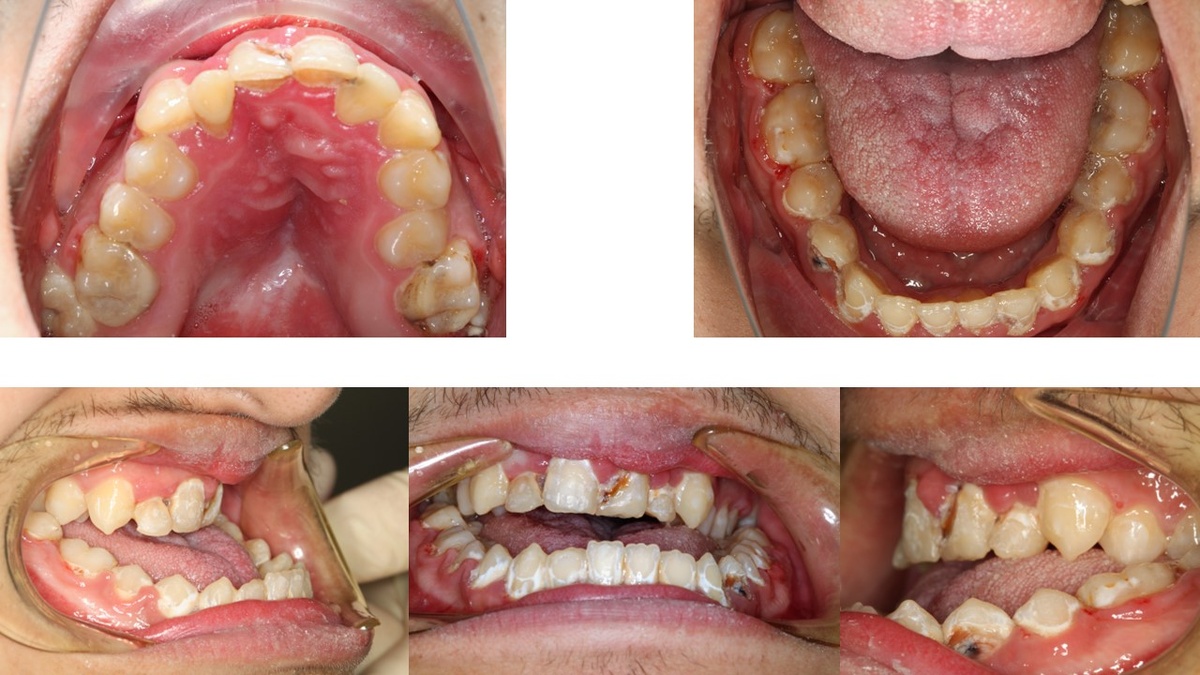

На прикус, на лицо, на улыбку, на зубы. Но не на жизнь! Что согласитесь радует! Он раньше лечился на брекетах, но почему-то не помогло. Зато помогло развитию кариесов прямо тотально на всех зубах! (Здесь и далее привожу размытые фото. При желании можно сделать "свайп" вправо.

"Небольшой" экстремальный вариант мезиального прикуса.

Потому что у пациента врожденная патология, под названием "расщелина твердого неба"!

Что это значит? Это значит что с рождения не срослись правая и левая половины верхней челюсти. Дефект закрыли мягкими тканями давным давно. В противном случае он бы просто погиб. Но кости там не было и никогда уже не будет!

Закрытие костного дефекта верхней челюсти приводит к рубцовым изменениям слизистой, что и является фактором формирования аномалии прикуса.